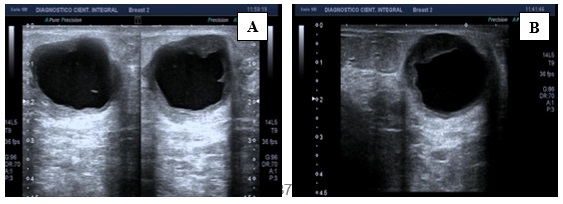

Características radiológicas en resonancia magnética

En la resonancia magnética estos tumores suelen exhibir características morfocinéticas que sugieren lesiones malignas. La mayoría de los estudios proporcionan información relevante para el análisis de las características morfológicas de los CMTN. Por lo general se presentan con alta señal en secuencias potenciadas en T2 e imágenes STIR (Short Time Inversion Recovery), principalmente centrales, lo que es indicativo de necrosis.(30)

En el estudio dinámico tras la administración de contraste intravenoso, estos tumores se manifiestan como áreas de captación tipo “masa” de aspecto heterogéneo, con realce de predominio periférico y engrosamiento cutáneo asociado. Las curvas de captación son en su mayoría tipo 2 o indeterminadas y tipo 3 (realce intenso con lavado posterior), con bajos niveles de Apparent Diffusion Coefficient (ADC), se acompañan de metástasis ganglionares en el 75% de los casos.(5, 10, 22, 23, 24, 25, 26, 27)

Características en RNM del CMTN

En los resultados de las características en resonancia magnética, se debe tener en cuenta que de las 17 pacientes solo se dispone información de 8 resonancias magnéticas realizadas en centros periféricos. Esto representa el 75% de la muestra, equivalente a 8 casos.

De estos casos se destaca que informan una cantidad de tejido fibroglandular tipo B, aunque no describen el realce parenquimatoso de fondo ni hallazgos asociados.

En lo que respecta a la descripción nodular, se encontró que en el 77,7% de los casos (7 de 8) el nódulo se reportó como redondeado, seguido de la forma ovalada.

Los márgenes del nódulo en 7 casos se describen como circunscritos y solo en 1 caso se reporta como espiculado.

Según lo referido realce interno del nódulo, 5 casos presentaron realce heterogéneo periférico y 3 casos mostraron un realce en forma de anillo.

Finalmente, en la evaluación de la valoración de las curvas cinéticas, se notó que en la fase inicial los 8 casos tenían una fase rápida. En la fase tardía, 6 de los casos presentaban un patrón de wash out, mientras que 2 casos mostraban un tipo de realce en meseta.

Anexo 3. Imágenes CMTN en resonancia magnética